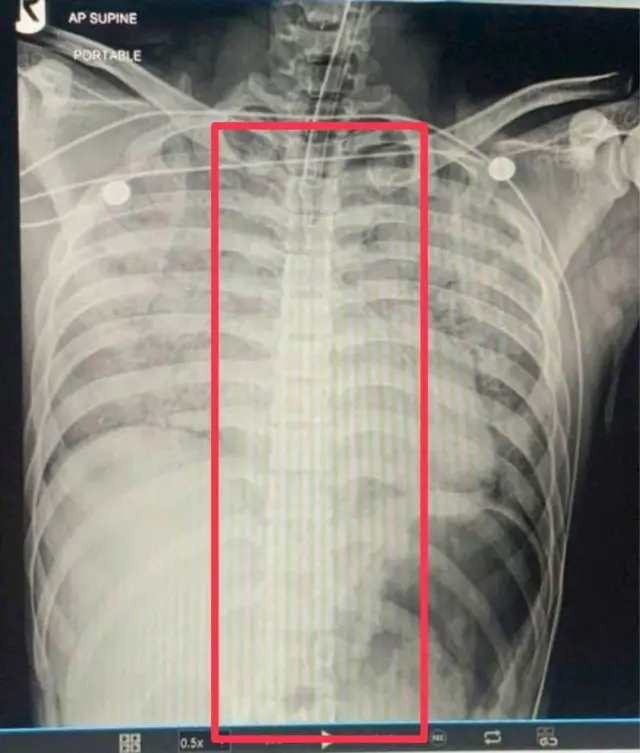

ในรายการ "มีเรื่องต้องคุย" ทางช่อง 7 HD วานนี้ (23 ก.พ.) ทาง พ.อ.อิทธินันท์ โชติช่วง ผอ. รพ.ค่ายจักรพงษ์ เปิดเผยเอกสารรายงานผลการชันสูตรพลิกศพพลทหารเพชรรัตน์ พร้อมกับไฟล์ภาพเอ็กซเรย์ช่องปอดของผู้ตาย

ในรายการเดียวกัน ร.อ.สาธิตย์ รุ่งโรจน์ นักเทคนิครังสีผู้เอ็กซเรย์ช่องปอดของผู้ตายก็บอกด้วยว่าไฟล์เอ็กซเรย์ไม่สามารถแก้ไขรายละเอียดผู้ทำการเอ็กซเรย์ได้ และยืนยันว่าภาพที่นำมาเปิดเผยต่อสื่อคือไฟล์เอ็กซเรย์ของพลทหารเพชรรัตน์

เขากล่าวว่าจากไฟล์ดังกล่าวก็ไม่พบช้อนสั้นอยู่ในภาพ และเห็นท่อช่วยหายใจทอดยาวลงมาจากช่องคอจนถึงช่องท้อง เพราะฉะนั้นเห็นได้ว่าไม่มีสิ่งกีดขวางอยู่บริเวณหลอดลมผู้ตาย